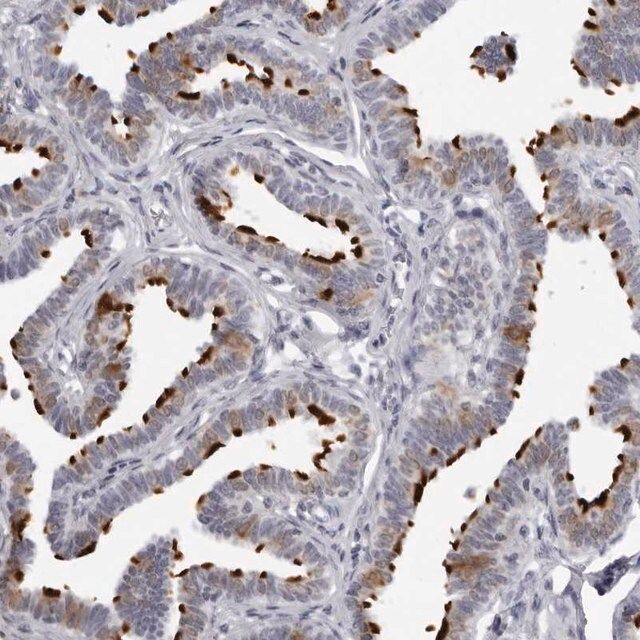

Anti-CDK1 antibody produced in rabbit, a Prestige Antibody, is developed and validated by the Human Protein Atlas (HPA) project (www.proteinatlas.org). Each antibody is tested by immunohistochemistry against hundreds of normal and disease tissues. These images can be viewed on the Human Protein Atlas (HPA) site by clicking on the Image Gallery link. The antibodies are also tested using immunofluorescence and western blotting. To view these protocols and other useful information about Prestige Antibodies and the HPA, visit sigma.com/prestige.

- IHC tissue array of 44 normal human tissues and 20 of the most common cancer type tissues.

| technique(s) | immunoblotting: 0.04-0.4 μg/mL immunofluorescence: 0.25-2 μg/mL immunohistochemistry: 1:200-1:500 |